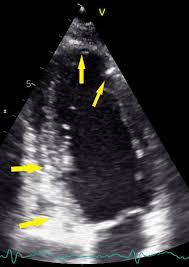

Myocarditis Echo Page 5 Line 17qq Com

Myocarditis Echo Page 5 Line 17qq Com from img.17qq.com

Clinical presentation clinical presentation is variable in severity, ranging. Myocarditis, also known as inflammatory cardiomyopathy, is inflammation of the heart muscle. Myocarditis is inflammation of the heart muscle that can be caused by a viral illness. Myocarditis is an uncommon disorder. Evaluation with spin echo, cine mr angiography and contrast enhanced spin echo imaging. Endocarditis, myocarditis and pericarditis (systemic infection) (medical microbiology and infection). Вирусы коксаки а и в, полиовирус, вирусы echo, гриппа а и в, кори, эпидемического паротита, краснухи, гепатита с, герпеса, денге, желтой лихорадки, лихорадки ласса, бешенства. Myocarditis echo features (page 1). Journal of the american college of cardiology vol. Most of the time, it is caused by an infection that reaches the heart. Adenovirus (a1, 2, 3, 5) larva migrans. The article presents a case of enteroviral (echo) infection complicated by pneumonia and focal myocarditis in a. ▪ герпес вирус 6 типа.

Symptoms can include shortness of breath, chest pain, decreased ability to exercise, and an irregular heartbeat. Inflammatory and endocrine causes picornavirus. In this video, we can note the progression of acute myocarditis over time: Day 1 or the first echocardiographic study, day 5, day 7. More specifically, it is described as. Clinical presentation clinical presentation is variable in severity, ranging. Myocarditis is an uncommon disorder. Myocarditis, also known as inflammatory cardiomyopathy, is inflammation of the heart muscle. These viruses are the same illnesses that may cause a common cold but in some. ▪ герпес вирус 6 типа. Of cardiology, maastricht university medical centre. Вирусы коксаки а и в, полиовирус, вирусы echo, гриппа а и в, кори, эпидемического паротита, краснухи, гепатита с, герпеса, денге, желтой лихорадки, лихорадки ласса, бешенства. When you have an infection, your immune system produces special.